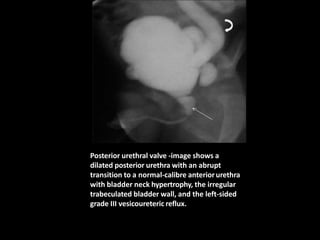

Posterior urethral valve -image shows a

dilated posterior urethra with an abrupt

transition to a normal-calibre anteriorurethra

with bladder neck hypertrophy, the irregular

trabeculated bladder wall, and the left-sided

grade III vesicoureteric reflux.